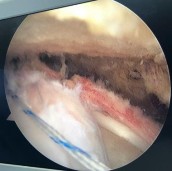

Hình phụ lục 2B:Hình ảnh rách rất rộng gân trên gai, dưới gai, khoảng gian chóp xoay; hình ảnh khâu khép rìa gân rách.

(Nguồn: BN nghiên cứu)

Đây là ca lâm sàng điển hình rách hình chữ U theo phân loại của Burkhart, nếu chỉ dựa trên phim CHT trước mổ thì rất khó xác định chính xác hình thái rách và dựa trên phim CHT trước mổ thì tiên lượng khâu được gân rất khó khăn, tuy nhiên sau khi nhận định hình dạng của gân rách chúng tôi tiến hành khâu khép rìa làm thu nhỏ gân rách tạo vi tổn thương tại diện bám, và khâu phục hồi vị trí bám của gân vào củ lớn xương cánh tay bằng 02 neo đôi. Trường hợp rách rất rộng này nếu không tiến hành khâu khép rìa gân rách mà tiến hành khâu kéo trực tiếp đầu gân rách về vùng diện bám sẽ khiến gân căng khó kéo và dễ tạo tai chó hai bên mép của vết rách. Với những trường hợp này khó xác định mốc để đặt neo nếu không dựa vào các mốc và các chỉ số giải phẫu về bờ ngoài gân.